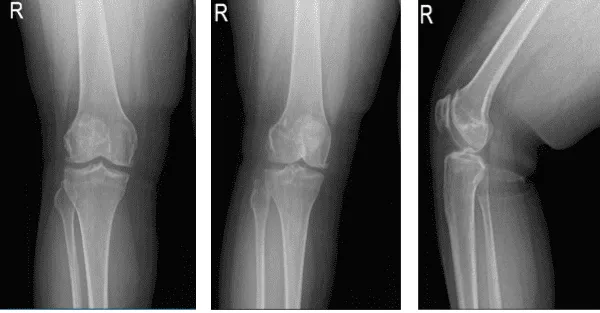

X-rays were done, the distal femur, patella, proximal tibia and proximal fibula demonstrate intact cortical margins with no acute fracture. The medial, lateral and patellofemoral joint spaces are well-maintained. There is mild medial osteophyte formation. There is mild patellofemoral osteophyte formation.

There is no radiographic evidence of a joint effusion. There is no radiographic evidence of soft tissue swelling. The impression is there are mild osteoarthritic degenerative changes. There are no acute fractures.

Which showed lateral tilt of the patella towards the trochlea along with advanced patellofemoral arthritis with mild medial compartment arthritis. Also, the MRI was done to confirm the findings.

Right knee X-ray AP Lateral and Oblique 3 views